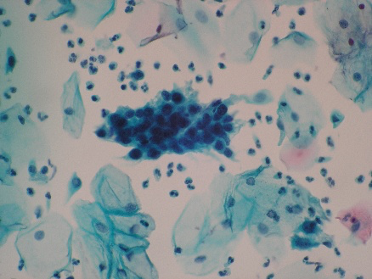

Ans to previous (November 2025):

Highly suggestive of papillary adeno-carcinoma Endometrium - Shows adequate cellularity with papillae of carcinoma cells showing hyperchromatic and pleomorphic nuclei, highly suggestive of papillary adenocarcinoma of the endometrium.